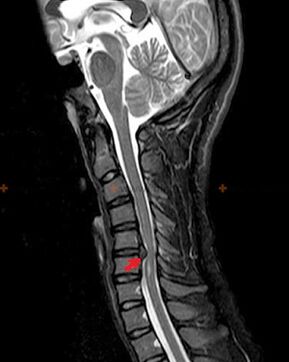

X-ray diagnosis and signs

Osteochondrosis is a radiographic diagnosis, since a detailed clinical picture is available only at the time of exacerbation, while changes in the spine can occur with complete subjective well-being of the person.Without an x-ray examination, we can only talk about suspicion of osteochondrosis, as similar symptoms can be caused by other diseases (myositis, vertebral neoplasms and others).

To diagnose osteochondrosis, the following research methods are used: radiography (preferably with functional tests), MSCT and MRI.The latter study is more preferable because it allows you to visualize the state of the intervertebral structures very clearly.

The presence of the changes described above, as well as changes in the structure of the intervertebral disc, detected by MSCT and MRI, serve as reliable signs that confirm the presence of osteochondrosis.